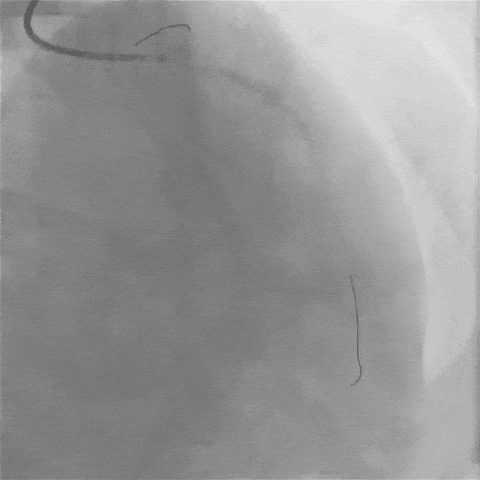

“必须立刻做急诊冠脉造影,明确血管堵塞位置和程度!”导管室副主任徐海祥当机立断,在与家属充分沟通并签署手术同意书后,王先生被紧急推入导管室。

图片

造影画面一出来,所有人都捏了把汗:左主干末段已高度狭窄,前降支近端更是完全闭塞,且血管壁上的钙化像 “铁板” 一样坚硬——这正是冠心病介入治疗领域公认的 “最后的堡垒”。